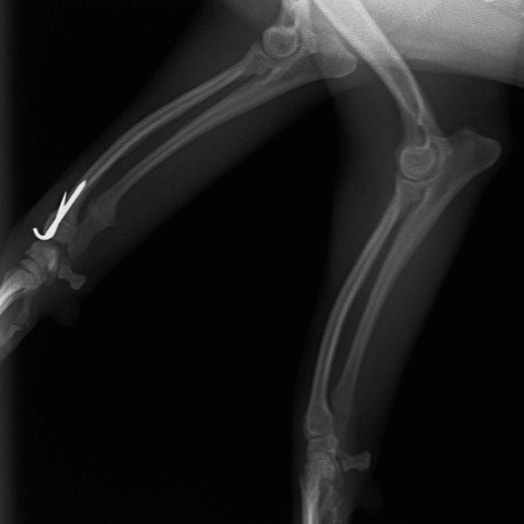

症例3:キルシュナーワイヤーのピンニングによる整復

ペルシャ猫 11ヶ月齢 雄

他院にて左大腿骨遠位の成長板骨折(salter-harrisⅠ型)が認められており、治療相談を目的として来院。当院にて、キルシュナーワイヤーを用いたピンニングにより骨折部位の整復を行いました。術後の経過は良好で、現在も経過観察中です。

術前レントゲン

術後レントゲン